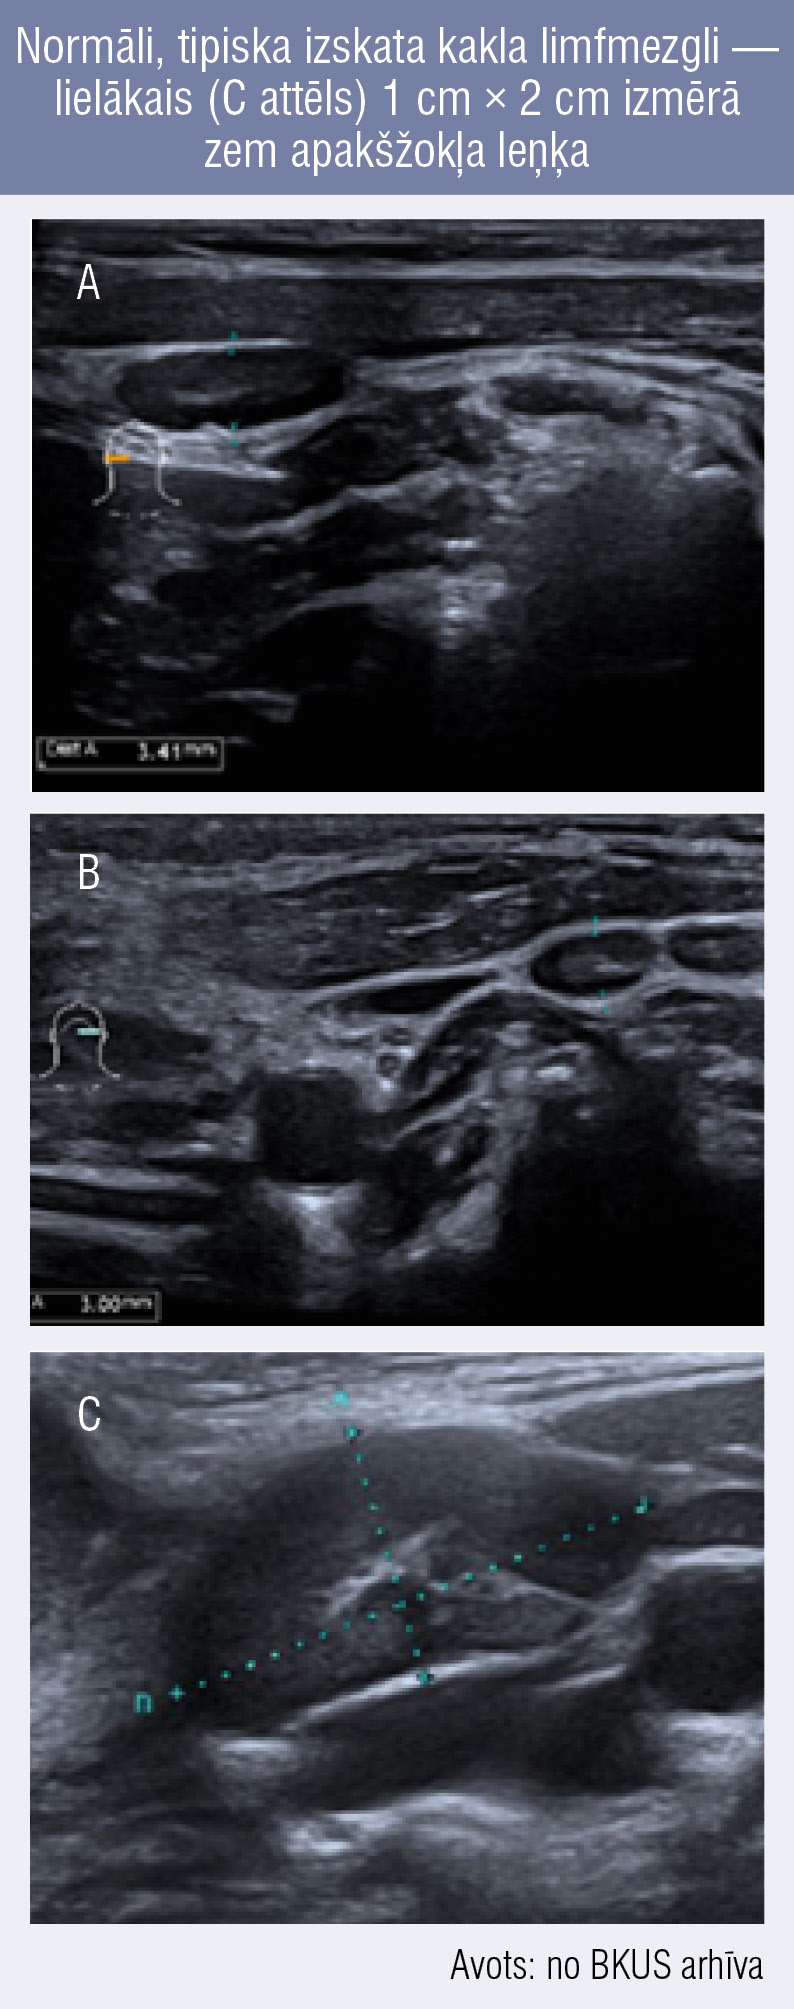

Normāli, tipiska izskata kakla limfmezgli —

lielākais (C attēls) 1 cm × 2 cm izmērā zem apakšžokļa leņķa Normāli, tipiska izskata kakla limfmezgli —

lielākais (C attēls) 1 cm × 2 cm izmērā zem apakšžokļa leņķa

Normāli, tipiska izskata kakla limfmezgli — lielākais (C attēls) 1 cm × 2 cm izmērā zem apakšžokļa leņķa

Tomēr neviens atsevišķs ultrasonogrāfijas izmeklējuma kritērijs nevar precīzi atšķirt labdabīgus vai ļaundabīgus limfadenopātijas cēloņus. [7] Ultrasonogrāfijā bērniem normāli limfmezgli vienmēr būs redzami. Normāla, neizmainīta izskata limfmezgla US atrade:

• skaidri norobežots,

• ovālas formas,

• ehogēns (gaišs) centrs jeb tauku sakne (hils) ar saglabātu hilāru vaskularizāciju krāsu doplera režīmā,

• īsākajā šķērsizmērā < 10 mm.

Normāls jugulodigastriskais limfmezgls, kas atrodas zem apakšžokļa leņķa (IIa kakla limfmezglu grupa), īsākajā šķērsizmērā var būt pat 15 mm (1. attēls). [8]